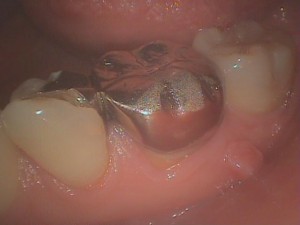

左下顎第一大臼歯です。

金属のクラウンがセットしてありますが、よく見ると歯肉がニキビのように腫れています。根の先が炎症を起こし、膿みの出口を求めて歯肉が腫れて来ます。

角度を変えると大臼歯の間にできています。